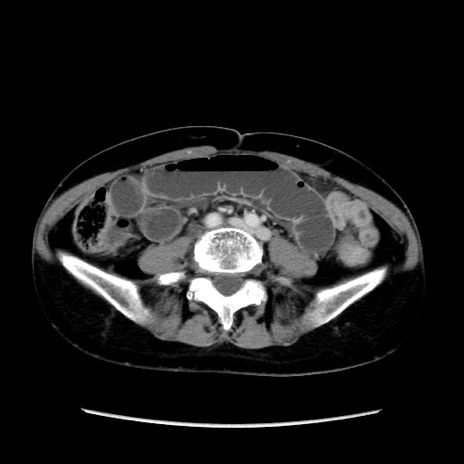

冠状断像

【症例】40歳代 女性

【主訴】上腹部痛、嘔気・嘔吐

【現病歴】約9時間前頃から急に上腹部痛、嘔気、嘔吐が出現。改善しないため救急要請。

【既往歴】子宮頚癌(広汎子宮全摘術、放射線療法)、腸閉塞

【身体所見】腹部:平坦、軟、腸雑音亢進、上腹部を中心に腹部全体に圧痛あり。

【データ】WBC 8400、CRP 0.03